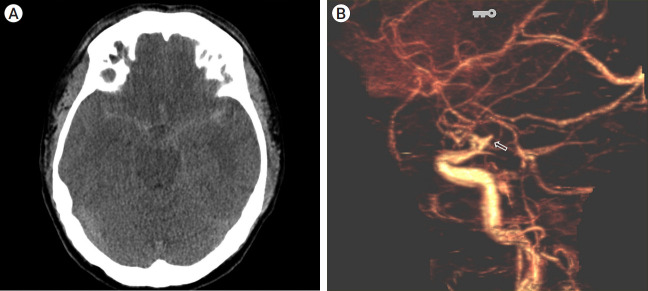

增生性脉络膜前动脉(AchA)是一种极为罕见的先天性血管变体,可被误认为是其他脑动脉。本病例报告介绍了一名38岁的男子,他表现出严重的突发性头痛,并被诊断为由增生性AchA引起的动脉瘤破裂。动脉瘤用线圈栓塞成功治疗,但8个月后发现复发,需要额外的手术干预。讨论强调了增生性AchA的分类,并强调了识别这种解剖变异以避免治疗过程中并发症的重要性。本病例报告强调了在脑动脉瘤治疗中对增生性AchA的认识和理解的必要性。

Hyperplastic anterior choroidal artery (AchA) is an extremely rare congenital vascular variant that can be mistaken for other cerebral arteries. This case report presents a 38-year-old man who presented with a severe sudden-onset headache and was diagnosed with a ruptured aneurysm originating from a hyperplastic AchA. The aneurysm was successfully treated with coil embolization, but recurrence was detected after eight months, leading to additional surgical intervention. The discussion highlights the classification of hyperplastic AchA and emphasizes the importance of recognizing this anatomical variant to avoid complications during treatment. This case report underscores the need for awareness and understanding of hyperplastic AchA in the management of cerebral aneurysms.